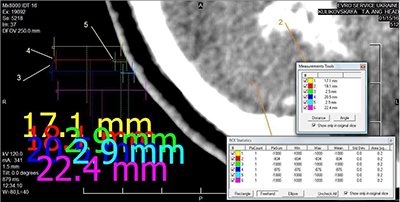

На рисунку 3 наведено результати вимірювання інструментами програми eFilm значень оптичної щільності чорного фону вздовж променя від краю зображення поперечного зрізу головного мозку пацієнтки К.

Розрахункові дані внесено до таблиці 3.

Ділянки Щільність (HU) % відповідності Відстань (мм) Різниця відстані (разів) 1 -1000 - 17,1 - По променю 2 -834 83,4 18,1 6,24 3 -1000 2,9 По променю 4 -876 87,6 20,5 7,07 5 -1000 2,9 6 -1000 - 22,4 -

Особливу увагу слід звернути на значення оптичної щільності поза зовнішніми контурами зображення об’єкта (чорний фон). Аналіз даних (рис. 3 та табл. 3) показав, що оптична щільність поза зображенням досліджуваної області («чорний фон», «нуль пікселів зображення») у першій парі по променю (2, 3) на відстані 18,1 мм дорівнює -834 HU, а на відстані 2,9 мм вона становить -1000 HU, тобто менша оптична щільність чорного фону знаходиться в 6,24 раза ближче до краю зображення поперечного зрізу черепа, ніж оптична щільність -834 HU, що суперечить очікуваній закономірності. У другій парі (4, 5) ця відстань ще більша – 7,07 раза.

Отже, оптична щільність чорного фону змінюється по променю від -1000 HU поблизу межі об'єкта, що досліджується, до -834 HU на відстані в 7 разів далі. Наявність ділянок різнорідної щільності поза зображенням зрізу, на тлі «абсолютного нуля», не виключає можливість аналогічних артефактів і на головному об'єкті – зображенні поперечного зрізу пацієнта. Це може негативно впливати на оцінку результатів лікування, а також на формування плану подальшої терапії, якщо в основу будуть покладені некоректні дані, оскільки дози для фотонної променевої терапії безпосередньо пов'язані зі значеннями Хаунсфілда (HU), отриманими з комп'ютерної томографії [47].